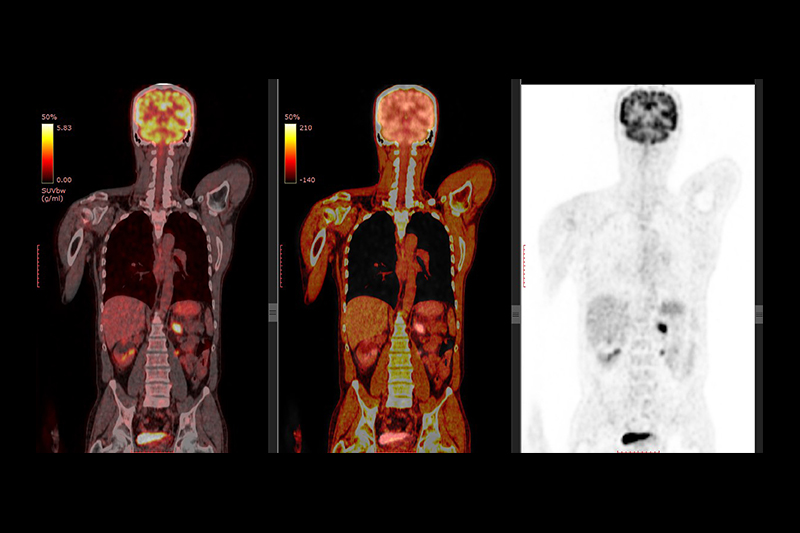

PET 正電子電腦斷層掃描(Positron emission tomography,PET Scan)

PET與上述三種檢查工具更不同,PET是一種核子醫學技術,病人需被注射一些具放射性的顯影劑,利用放射性同位素在衰變過程中放射的正電子,以及其與「目標物」發生的一連串化學反應,再以機器分析成像。

上段使用了「目標物」一詞,那是因為PET通常應用於腫瘤檢查上,事實上,病人檢查前所注射的顯影劑是具有追蹤性,能夠自動追蹤並積聚於癌細胞之處,然後發出信息,讓掃描儀器能夠檢測出來,將癌細胞的分佈、數量等情況成像。

說到危險性,難免令人擔心PET會否對人體造成損害,畢竟用到了放射性物質。不過其實PET Scan是很安全的檢查工具,檢查用到的放射性物質劑量相當低,事實上日常環境的輻射量比PET用到的更多。即使真的出現不良反應,也只是輕微的噁心、紅疹等,並不會致命。順帶一提,現時臨床多用到的其實是結合PET與CT的器材,一般喚作PET-CT,是結合了兩種檢查方式的優勢,提高檢查的準確率。